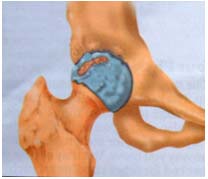

• 关节破坏的X线改变

关节软骨破坏,关节间隙消失               股骨颈骨折,容易发生不愈合